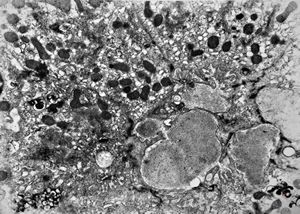

M,16y. | lipofuscin - hyperbilirubinaemia - Gilbert or Dubin-Johnson syndrome

M,17y. | lipofuscin - hyperbilirubinaemia - Gilbert or Dubin-Johnson syndrome

M,17y. | hyperbilirubinaemia - lipofuscin - Gilbert or Dubin-Johnson syndrome

F,12y. | lipofuscin - hyperbilirubinaemia - Gilbert or Dubin-Johnson syndrome